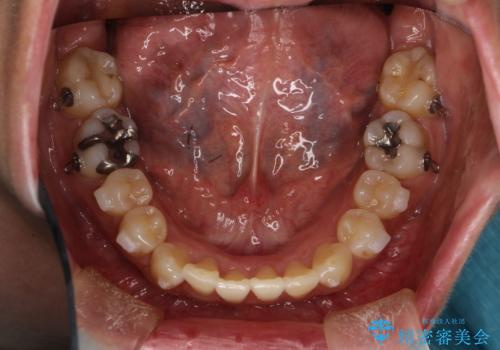

マウスピース枚数 初回52枚 + 追加19枚 + 追加12枚

概ね2年での治療完了となりました。

上の歯列に後方への力をかけるために、患者様には顎間ゴムをマウスピースと共に併用してもらいました。

当院独自の工夫を随所に盛り込み、狙い通りの治療結果が得られました。